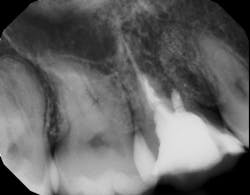

Saving compromised multirooted teeth with root amputation can often be successful, but the technique is sensitive and complex. Proper case selection is essential, and considerations include the following:

There is sufficient bone support around the remaining roots (at least 50% or more is needed) along with sufficient coronal tooth structure (figure 3).How does root amputation compare with other surgical procedures?